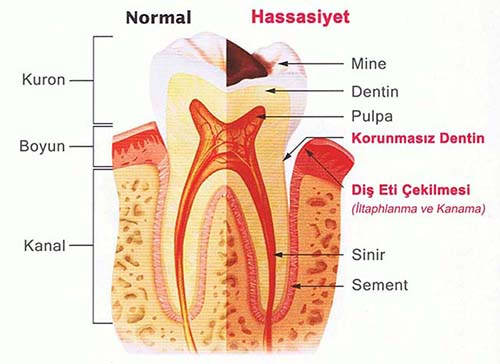

Diş çürüğü bitkisel tedavi. Bitkisel tedavi yumurta kabukları i̇le diş çürüğü tedavisi yumurta kabukları i̇le diş çürüğü tedavisi. Mineral kaybı devam ederse dişin yumuşak içi kısımları da etkilenir ve diş çürüğü meydana gelir. Diş ağrısı geçici olup oldukça rahatsı edicidir. Diş çürümesinin erken evrelerinde florür hasarlı diş minesini de onarabilir.

Macunların kullanımı yanı sıra beslenmenize de özen göstermelisiniz. Kalsiyum deposu olan yumurta ile diş çürüklerini tedavi etmek mümkün. Uygulamak tamamen size kalmış olup kullanılan tedaviler kesin bir sonuç. Dişin iç pulpasını etkilemeyen diş minesindeki boşluklarda dolgu kullanılabilmektedir.